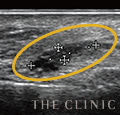

しこり除去の際はエコーを使用

しこりはヒアルロン酸溶解注射・ヒアルロニダーゼで溶かします。しこりの除去には必ずエコーを使用し、しこりに的確に注射を行います。小さいしこりの場合は、溶解されれば自然と吸収されますが、当院では本当に吸収されたか、後日エコー検査で確認を行い、術後の仕上がりとゲストの健康状態に責任を持ちます。